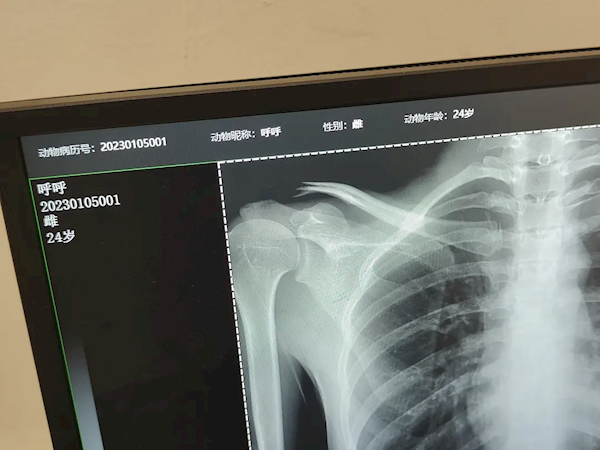

近日,一位豆瓣网友分享了一段让网友笑喷的经历,因为医院拍片子排队的人太多,懒得排队的她就跑到宠物医院给肺部拍了个片子。

据该女子表示,男朋友是宠物医院兽医,在建档时,给自己昵称填了“呼呼”,24岁,雌性。

网友直接笑喷:哈哈哈 呼呼 24 雌 好可爱

该女子还提醒大家不要学自己,需要拍片子的话还是得去医院让医生给你看看片子!!

对于用宠物设备给人拍片的行为,医生提醒:这种方法不可取,因为设备的放射剂量不同,对人体可能存在一定危害,而且拍片的成像质量也不能保证。